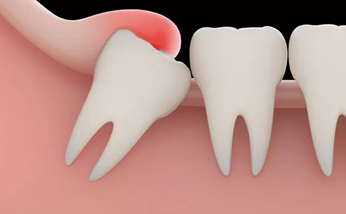

親知らずとは?

親知らずは「智歯」や「第三大臼歯」とも呼ばれ、お口の中の一番奥に生えてくる永久歯です。永久歯の中で最後に生えてくる歯であるため、生えてくるスペースが足りず横向きや斜めに傾いて生えたり、顎骨の中に埋まったまま生えてこないといった場合(埋伏智歯)もあります。

そうした親知らずは、歯肉の炎症を引き起こす原因になったり、隣の第二大臼歯の虫歯リスクを高める原因にもなり、歯並びに悪影響を及ぼすケースもあるため、精査したうえで抜歯をおすすめする場合があります。

親知らずの抜歯

親知らずが斜めに生えて痛みがあったり、隣の歯を圧迫している場合など、周囲の歯に及ぼすリスクも考慮して、親知らずの抜歯が必要になる場合があります。